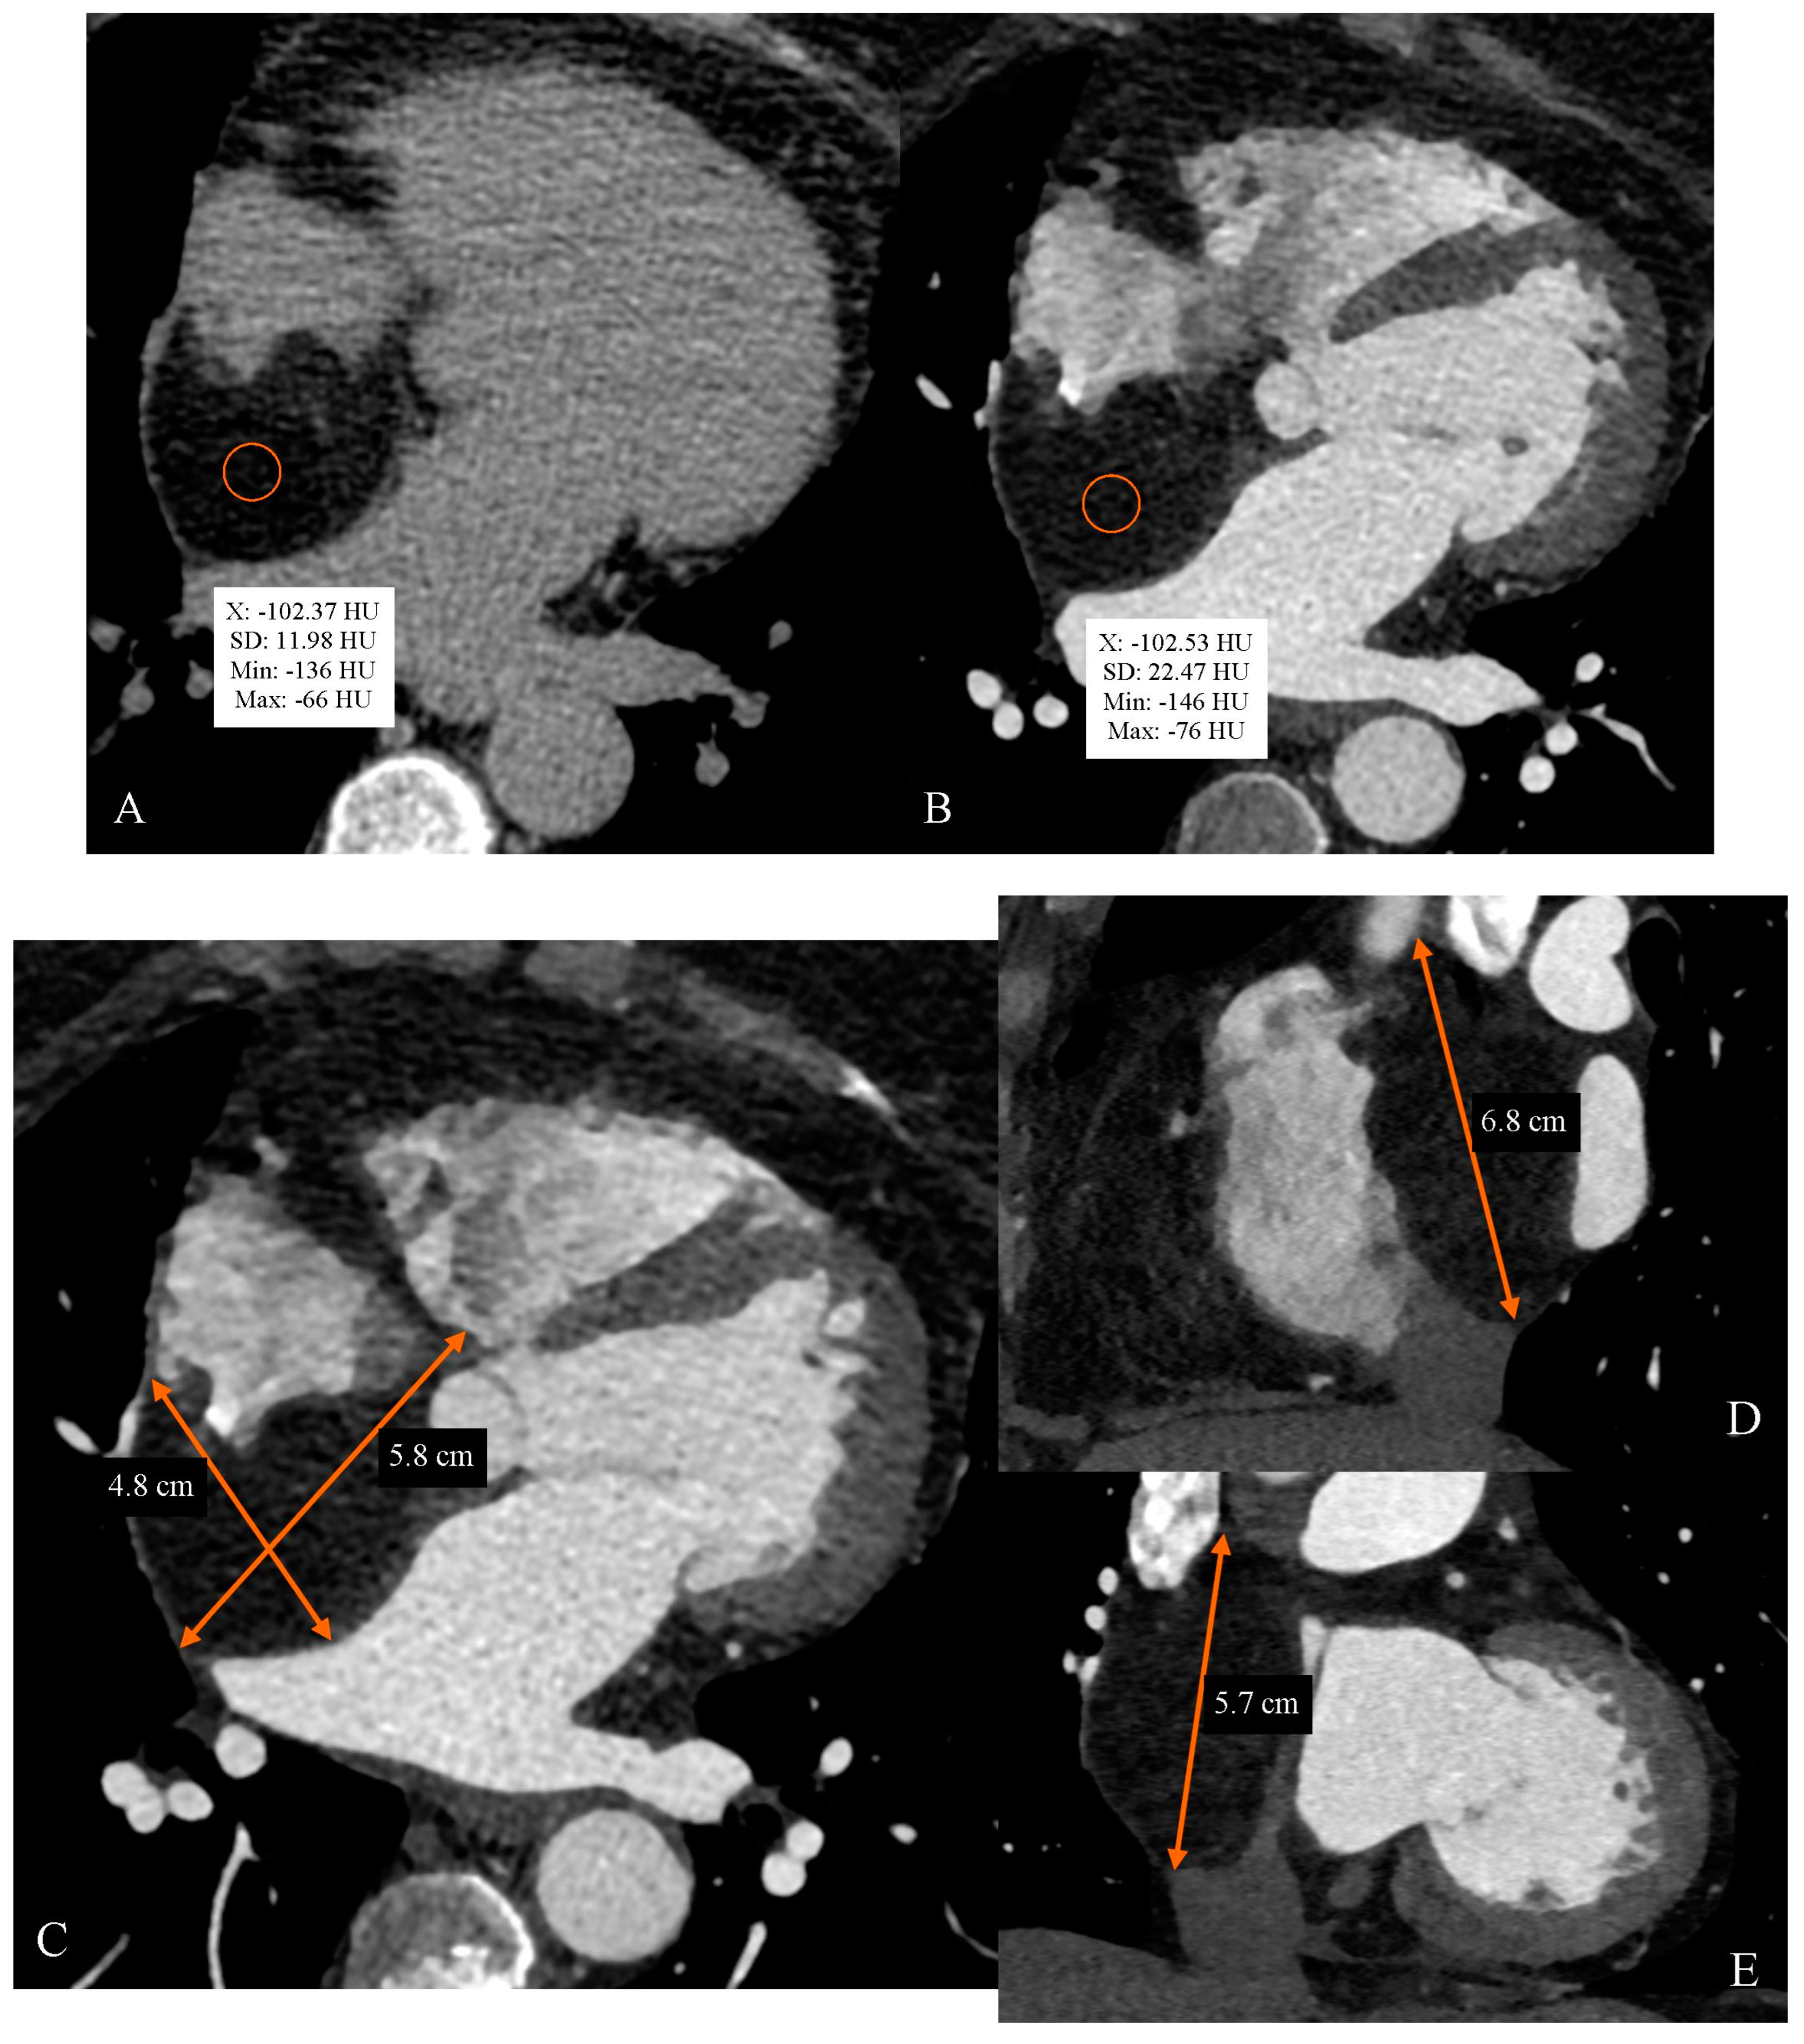

Cardiac Computed Tomography as a Method of Diagnosing the Type of Cardiac Tumor—Example of Interatrial Septal Lipoma Filling the Right Atrium

Gać, P.; Jaworski, A.; Parfianowicz, A.; Surma, A.; Jakubowska-Martyniuk, A.; Żórawik, A.; Poręba, R. Cardiac Computed Tomography as a Method of Diagnosing the Type of Cardiac Tumor—Example of Interatrial Septal Lipoma Filling the Right Atrium. Diagnostics 2024, 14, 2496. https://doi.org/10.3390/diagnostics14222496